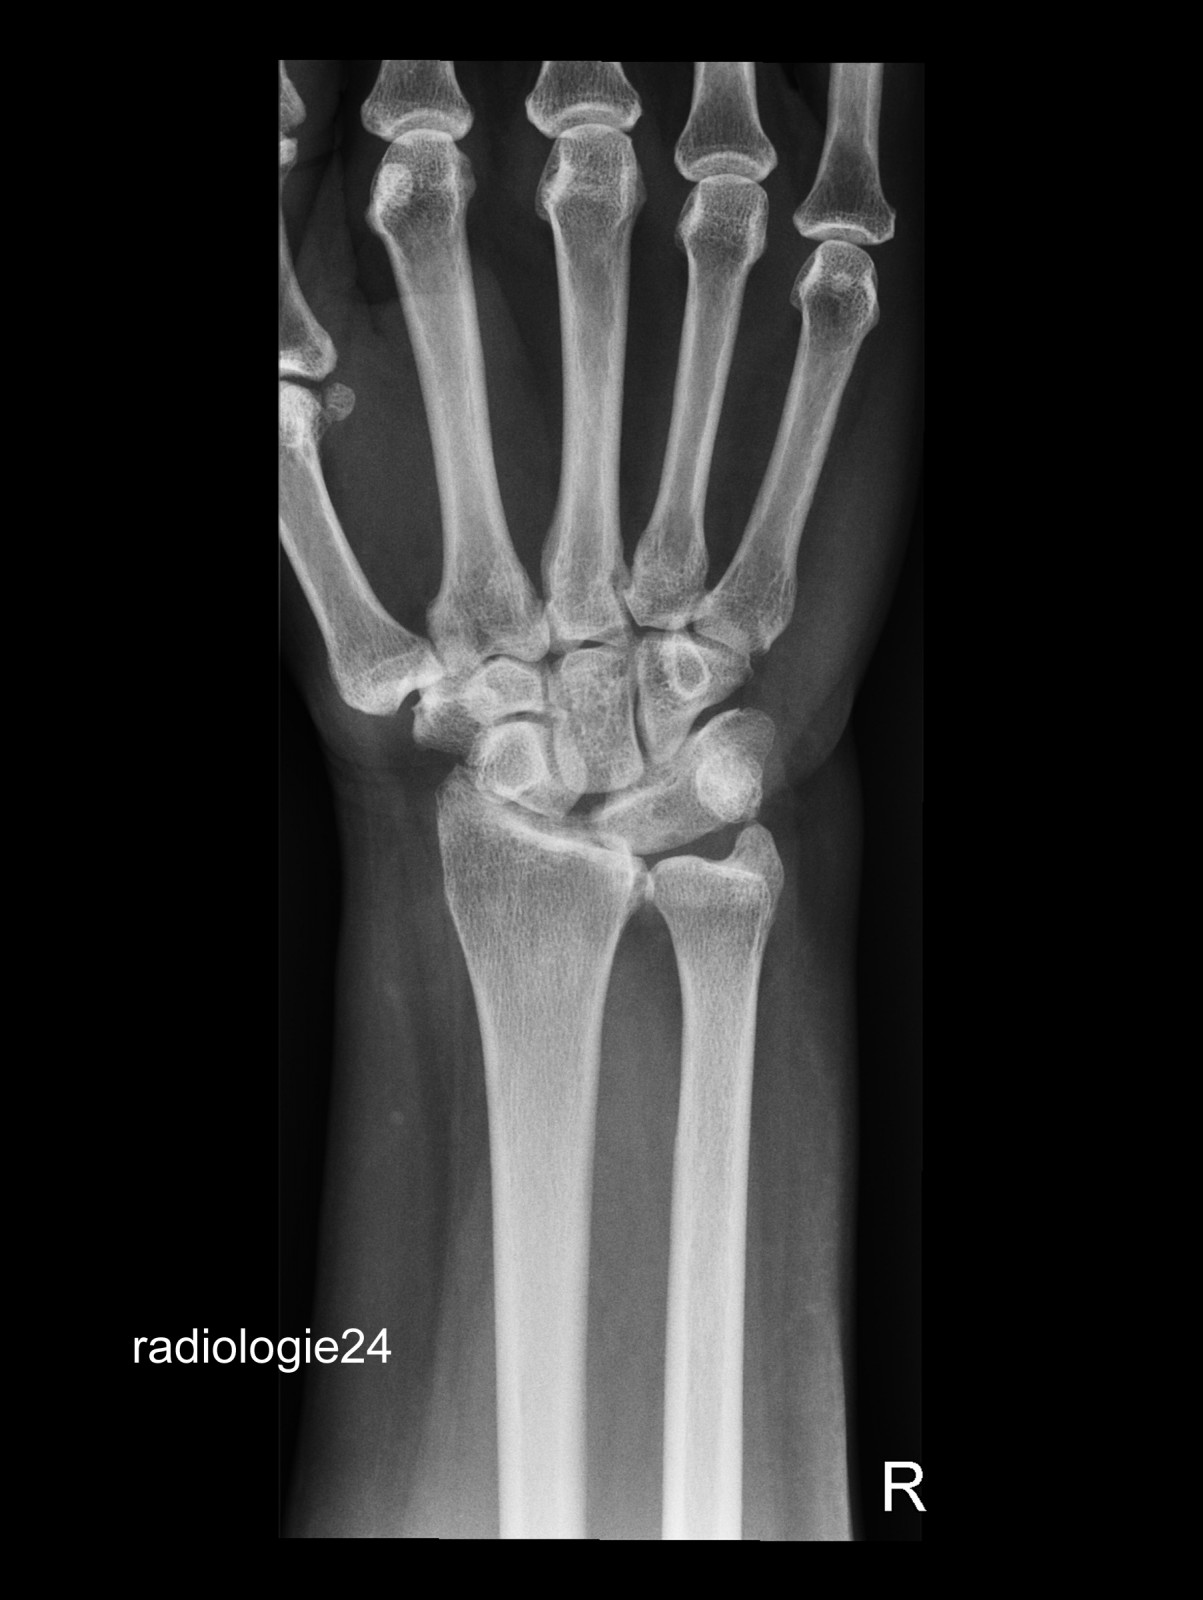

Röntgenfall des Monats